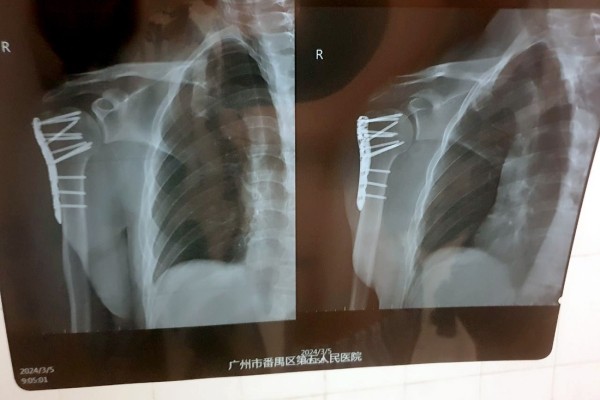

— Рука начала стремительно синеть, мне сразу сделали рентген и МРТ. Достаточно быстро стало понятно, что у меня перелом плеча со смещением. Боль была очень сильная, я не мог нормально пошевелить рукой. Врач сказал, что, возможно, потребуется операция. Мне пытались вправить плечо, но безуспешно. В итоге направили в хирургический отдел стационара, — говорит собеседник.

Операцию все-таки пришлось сделать. По словам врачей, в противном случае кости срастались бы очень долго.

— Все это заняло около двух часов. Процесс не был приятным, так как я был в сознании и ощущал все манипуляции, проводимые на костях моего плеча, включая сверление, например. Была установлена пластина, которая зафиксировала поврежденные кости в правильном положении. После операции побочных эффектов не было, однако в течение еще шести часов врачи подключали различные датчики для контроля состояния. Все это время нельзя было есть и пить. А рука ощущалась как кусок бревна, — вспоминает читатель.

— Китайские врачи проделали по-настоящему хорошую работу. Это подтвердил знакомый белорусский хирург, взглянув на мои послеоперационные снимки. Думаю, не последнюю роль в этом сыграло и то, что я иностранец: мне показалось, что врачи особенно старались сделать все по высшему разряду. Также это хороший пример того, что надо смотреть не на вывеску больницы. Главное — это именно врачи и их отношение к своей работе, — считает молодой человек.

Белоруса выписали из больницы спустя три дня после операции. Впереди длительная реабилитация и еще одна операция — для того, чтобы изъять из плеча металлическую пластину.